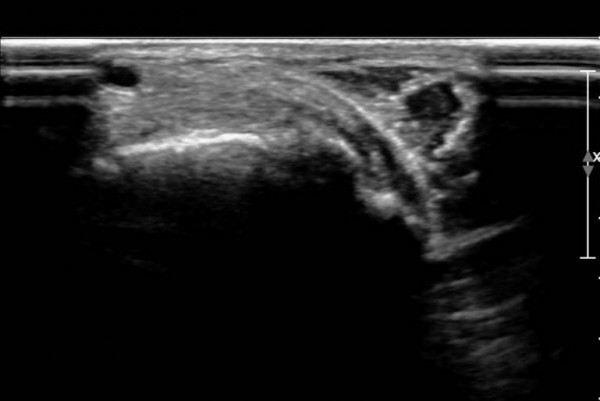

ÃÊÀ½ÆÄ ¼Ò°ß :  Àü°æ°ñ°Ç Á¾´Ü¸é°Ë»ç¿¡¼­ Àü°æ°ñ°ÇÀÌ °í¿¡ÄÚ¼¶À¯È­(hyperechoic fibrillar pattern) ¾ç»óÀ¸·Î °üÂûµÇ´Âµ¥

¼³Çü°ñ ºÎÂûºÎ¿¡¼­ °æ¹ÌÇÑ Á¦¿¡ÄÚ ¾ç»óÀÌ °üÂûµÈ´Ù(»çÁø 1, 2).